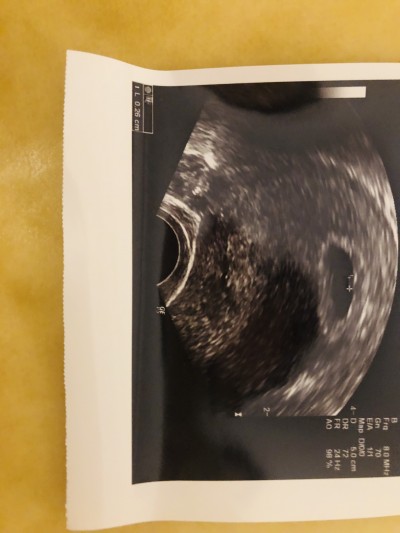

Merhaba arkadaşlar lütfen bir şeyler söyleyin içim içimi yiyor dün doktora ilk muayene için gittim bebeği normal ultrasonla göremedi keseyi gördü ama kesen büyük dedi sürekli sonra alttan muayeneyle baktı kesenin içinde 2 mm bir şey gördüm ama olumlu bir şey demek için çok erken dedi ve tekrar etti kesen büyük diye içim de korku olarak kaldı keseyi büyük görüp bebeği keseye göre küçük mü gördü anlayamadım sordum bir şey demedi özel doktordu birde.